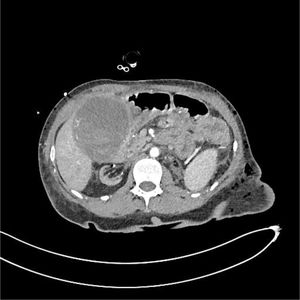

Paciente mujer de 47 años con antecedentes de nefropatía por inmunoglobulina A (IgA) que requirió trasplante renal en dos ocasiones y hemicolectomía derecha por perforación intestinal, en el posoperatorio inmediato de nefrectomía izquierda por neoplasia renal, presenta shock hipovolémico secundario a colecistitis necro-hemorrágica evidenciando sangrado activo en la tomografía axial computarizada (TAC) (figs. 1 y 2) realizada por sospecha de hemorragia posquirúrgica. Se efectúa una colecistectomía emergente encontrando 500 cc de contenido hemático en el interior de la vesícula y sangrado activo en el peritoneo parietal de la misma que cede tras la ligadura de la arteria cística. La paciente es dada de alta sin sufrir complicaciones.